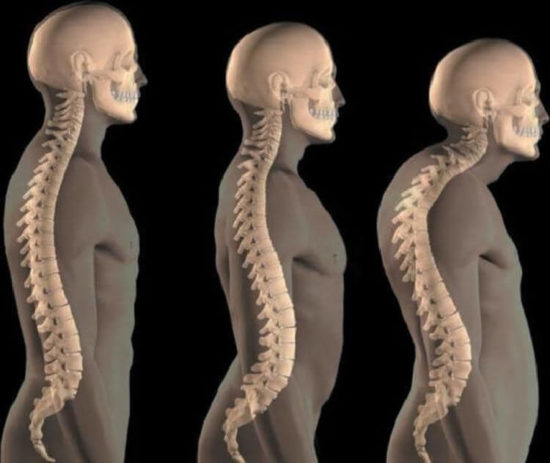

Измерение кифоза грудного отдела: Рентгеновские снимки